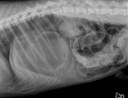

RadioQuiz 14 – Mon chien traîne de la patte

RadioQuiz 13 – Donnez-lui un petit sac

RadioQuiz 12 – Mon chat ne file pas

RadioQuiz 11 – Bulldog traînant d’la patte

RadioQuiz 9 – Carlin portant est de partir du bon pied !

RadioQuiz 8

RadioQuiz 7

RadioQuiz 6 – Ma p’tite chienne a mal à la patte

RadioQuiz 5

RadioQuiz 4